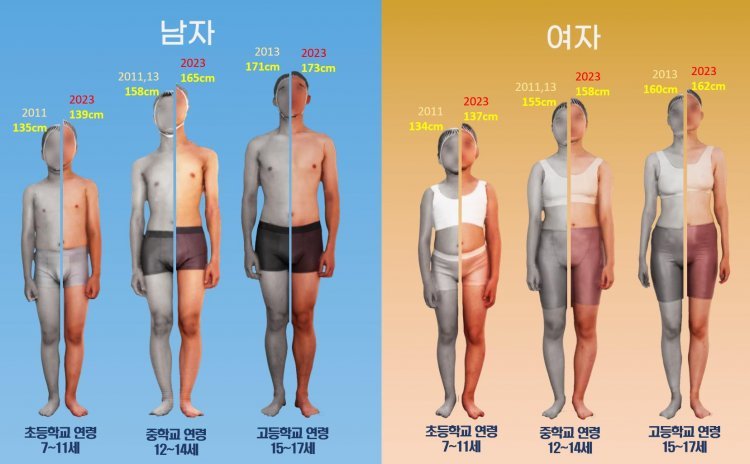

제대혈 줄기세포 이식수술은 손상된 무릎 관절에 새로운 연골 조직이 자라게 해 관절염을 개선하고, 무릎 활동성을 회복하는 데 도움을 준다. 사진은 박재영 선정형외과 원장의 제대혈 줄기세포 이식 수술 장면. 선정형외과 제공

제대혈 줄기세포 이식수술은 손상된 무릎 관절에 새로운 연골 조직이 자라게 해 관절염을 개선하고, 무릎 활동성을 회복하는 데 도움을 준다. 사진은 박재영 선정형외과 원장의 제대혈 줄기세포 이식 수술 장면. 선정형외과 제공

제대혈 줄기세포 이식수술은 손상된 무릎 관절에 새로운 연골 조직이 자라게 해 관절염을 개선하고, 무릎 활동성을 회복하는 데 도움을 준다. 사진은 박재영 선정형외과 원장의 제대혈 줄기세포 이식 수술 장면. 선정형외과 제공

제대혈 줄기세포 이식수술은 손상된 무릎 관절에 새로운 연골 조직이 자라게 해 관절염을 개선하고, 무릎 활동성을 회복하는 데 도움을 준다. 사진은 박재영 선정형외과 원장의 제대혈 줄기세포 이식 수술 장면. 선정형외과 제공#신모 씨(61)는 의자에서 앉았다 일어나는 것부터 계단을 오르내리는 것까지 일상적인 움직임이 힘들었다. 동네 정형외과와 대학병원을 다니며 치료법을 찾아봤지만 대부분 인공 관절 수술을 권유했다. 하지만 신 씨는 재수술 위험이 있는 인공 관절 수술을 선뜻하기 어려웠다. 그러다 재작년, 선정형외과에서 제대혈(탯줄 혈액) 줄기세포 이식 수술을 알게 됐다. 우선 왼쪽 다리부터 줄기세포 이식 수술과 ‘휜 다리 절골술’을 받았다. 수술 후 통증이 줄고, 일상생활에 만족스러운 결과를 얻은 신 씨는 작년에 추가로 오른쪽 다리에 줄기세포 이식 수술을 받았다.